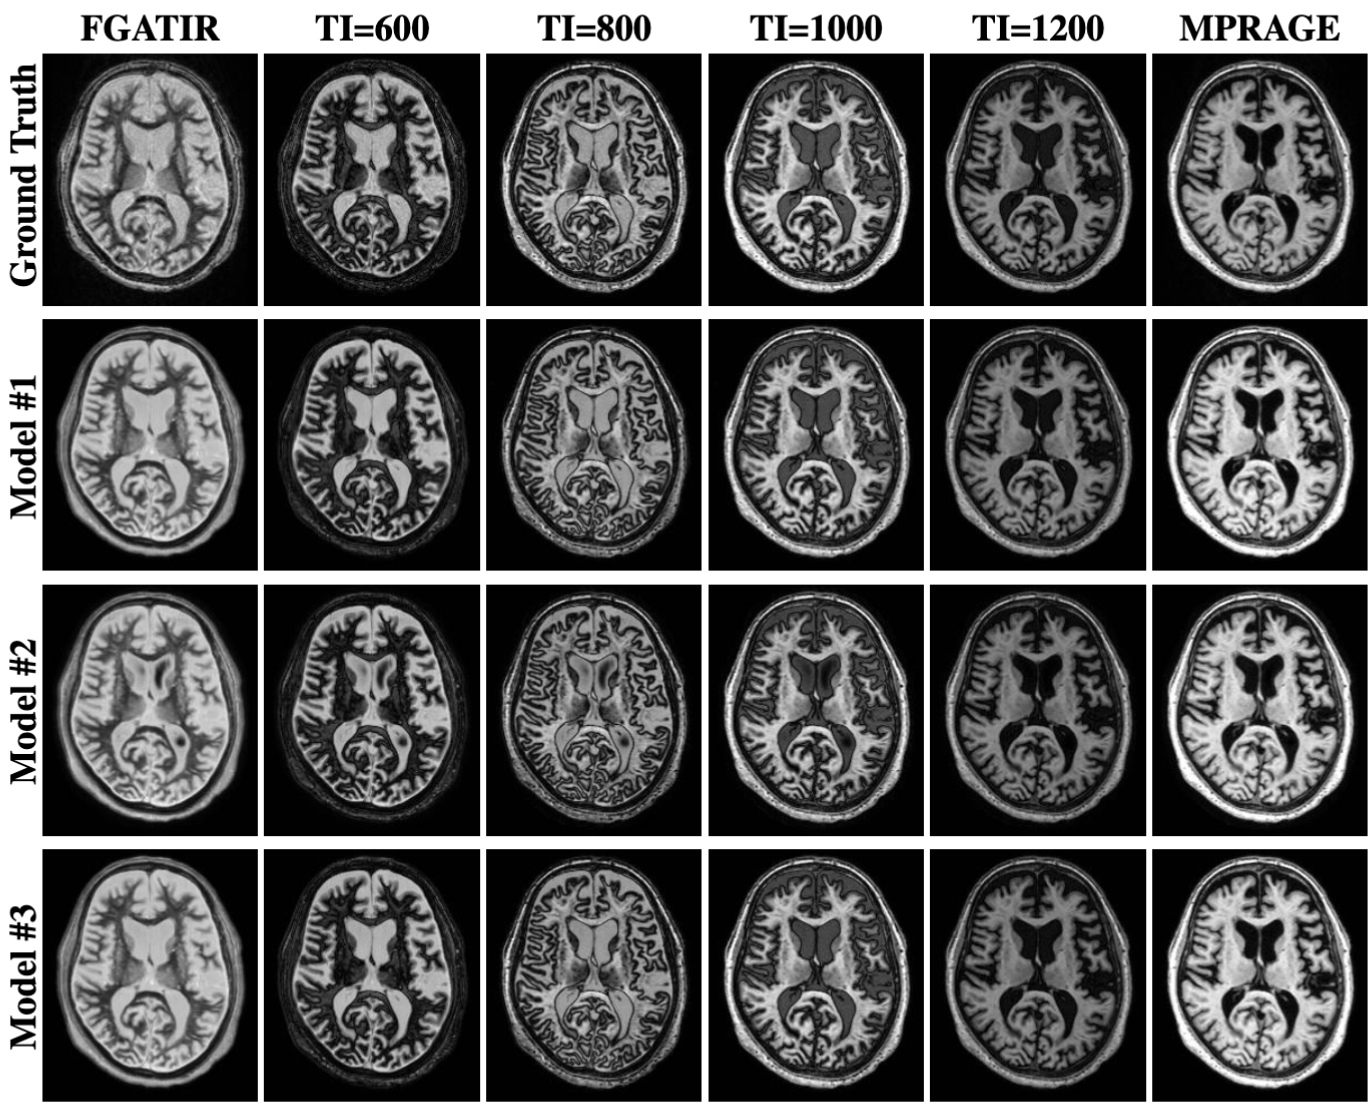

3.2 Multi-TI synthesis for in-domain testing dataset

Figure 8 shows examples of multi-TI images computed from the T1T1 and ρ\rho maps corresponding to the ground truth and the three SyMTIC models. Figure 9 provides a visual comparison of an acquired and synthetic MPRAGE and FGATIR images in the axial, sagittal, and coronal planes. We highlight DBS targets in these images, demonstrating that these structures are clearly visible in both the acquired and synthetic FGATIR images. This qualitative comparison supports the potential of our model to enhance DBS planning through synthetic FGATIR image generation.

Refer to caption

Figure 8: Synthetic multi-TI images of a test subject calculated using the predicted parameter maps from the SyMTIC models in Fig. 6.